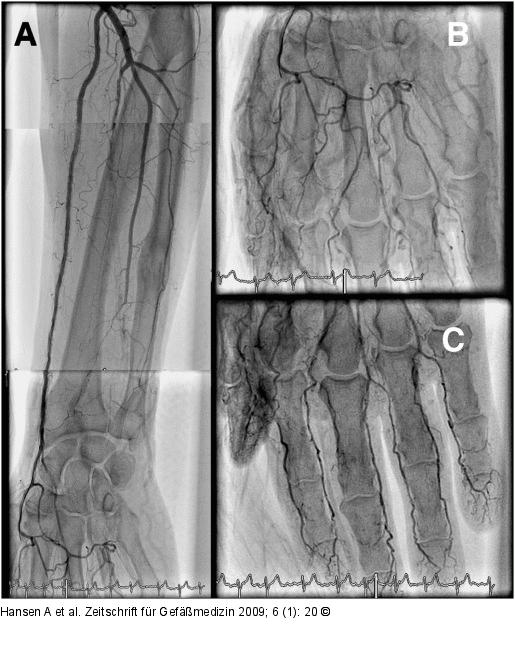

Abbildung 2a-c: Arteria radialis Postinterventionell rekanalisierte A. radialis (A) mit regelrechter Perfusion des Handbogens (B) und Ausschluss von peripheren Embolien im Bereich der Interdigitalgefäße (C) (Unterarm wurde für bessere Darstellung gedreht). |

Postinterventionell rekanalisierte A. radialis (A) mit regelrechter Perfusion des Handbogens (B) und Ausschluss von peripheren Embolien im Bereich der Interdigitalgefäße (C) (Unterarm wurde für bessere Darstellung gedreht). |